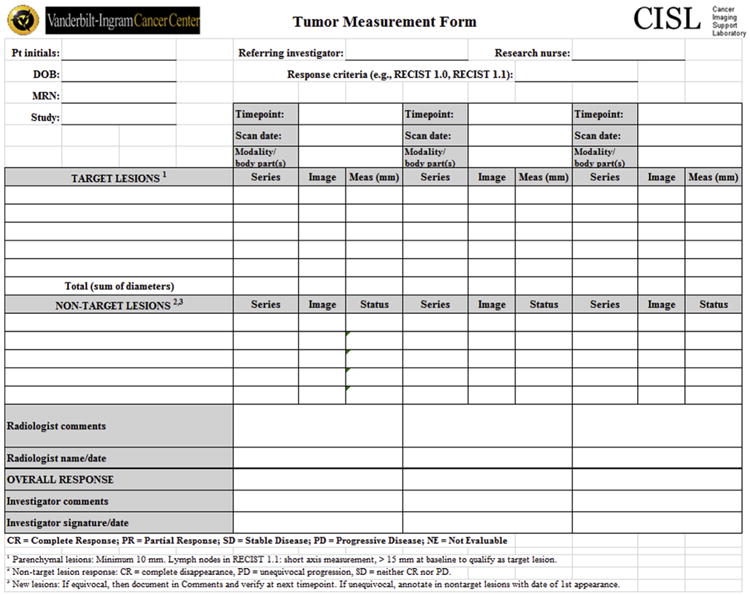

Figure 9.

Standard CISL tumor measurement form for Response Evaluation Criteria in Solid Tumor data extractions.